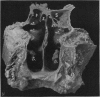

IV. The Anatomy of the Inferior Ethmoidal Turbinate Bone with Particular Reference to Cell Formation; Surgical Importance of such Ethmoid Cells